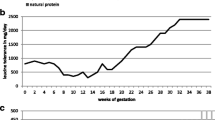

At 20 months of age, 5 months after the transplant, he presented to our center with symptoms of gastroenteritis and dehydration. He was admitted for intravenous rehydration for 1 day and went home. Three days later, he developed lethargy, convulsions, and encephalopathy requiring intensive management with high calories, BCAA-free medical foods, supplementation of isoleucine and valine, insulin administration and peritoneal dialysis. The amino acid profile of the initial admission for gastroenteritis reached us after a few days and showed elevated leucine (991 μM, normal range 73–161), isoleucine (521 μM, normal 46–90), valine (1,162 μM, normal 149–277) and alloisoleucine (detected). The amino acid profile at the time of encephalopathy and convulsions showed leucine (2,001 μM, normal range 73–161), isoleucine (877 μM, normal 46–90) and valine (1,653 μM, normal 149–277). His ALT was 30 IU/L (normal range 11–39) and his AST was 35 IU/L (normal range 22–58); the other liver tests were also normal. His ammonia level was 46 μmol/L. Liver Doppler study was normal, including the hemodynamic status of both arterial and venous vasculature. He recovered within 48 h and resumed his normal diet, without any protein restriction. His amino acid profiles during the illness are shown in Fig. 1.

Concentrations of branched-chain amino acids (BCAA) in plasma after liver transplantation in the index case. BCAA increased with acute dehydration evolving into encephalopathy (horizontal arrow) followed by normalization of BCAA on unrestricted diet after 48 h of intensive metabolic management (vertical arrow). The Y-axis indicates the BCAA plasma concentrations in μM/L and the X-axis days posttransplantation when patient presented with metabolic crisis

After that crisis, he remained well on a normal protein diet. His BCAA were done repeatedly and remained within the normal range.

At the age 26 months, 10 months after the transplantation, he presented again with an episode of seizures. This was his third one, after the one shortly after transplantation, which was attributed to tacrolimus toxicity, and the second one, 5 months after transplantation, while he was on unrestricted protein intake. This third episode was described as tonic movements of the right leg with uprolling of the eyes lasting for about 1 min. The amino acid profile on admission showed elevated leucine (990 μM, normal range 73–161), isoleucine (461 μM, normal 46–90), valine (892 μM, normal 149–277) and alloisoleucine (detected). Interestingly, a routine amino acid profile had been done 2 days prior to the admission. It was completely normal with leucine (66 μM, normal range 73–161), isoleucine (61 μM, normal 46–90) and valine (154 μM, normal 149–277). The patient recovered nearly completely within 24 h with IV fluids and his medical food. Since then, he again has been doing very well on normal diet. His last amino acid profile showed leucine, isoleucine, and valine values of 122, 53, and 145 μM, respectively; all are normal.